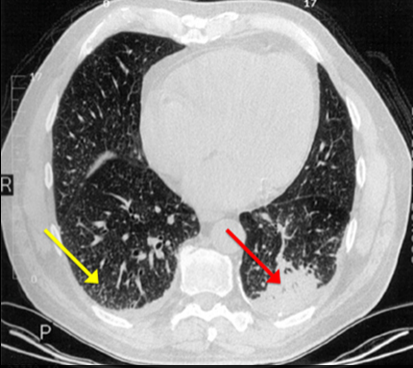

【读片园地】以双肺弥漫结节为表现的免疫功能正常者肺毛霉病

图片尺寸1080x693